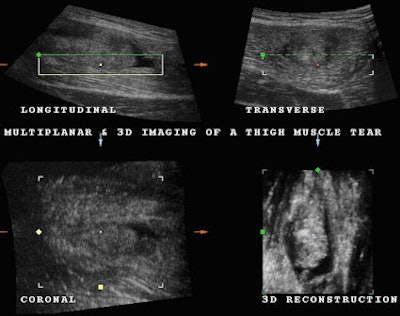

Once the location of the tear was determined, we decided to perform a 3D volume acquisition to better study the condition of the muscle and the full extent of the tear. Three-dimensional volume acquisition permits one to scroll backward and forward and up and down through the acquired volume.

The coronal plane permits a frontal view traditionally unavailable in ultrasound scanning that frequently allows a better appreciation of the extent of a tear (Fig. 2). As with many modern imaging modalities, 3D reconstruction is used to demonstrate both normal and abnormal anatomy. In this particular case, the complete separation of the muscle fibers from the point of insertion is well demonstrated along with a large hypoechoie fluid collection and coagulation material with the use of the coronal plane and 3D reconstruction (Fig. 3 and 4).